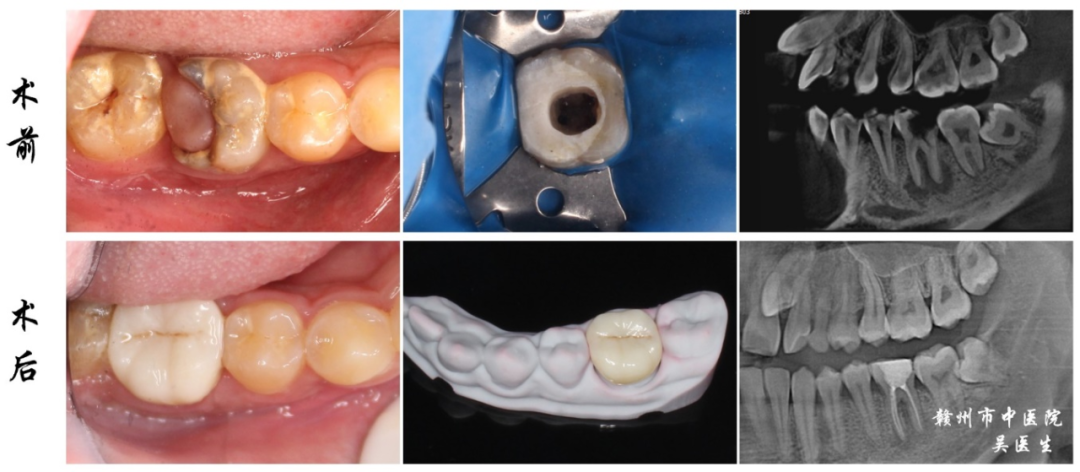

5.CT在根管治疗中的应用

显示单颗患牙内的3D根管形态和牙髓腔形态,直观地观察到患牙的牙根数量、形态、粗细,以及是否有钙化、分叉、侧支根管等,三维可视化的阅片诊断帮助医生实现更精准的根管治疗。